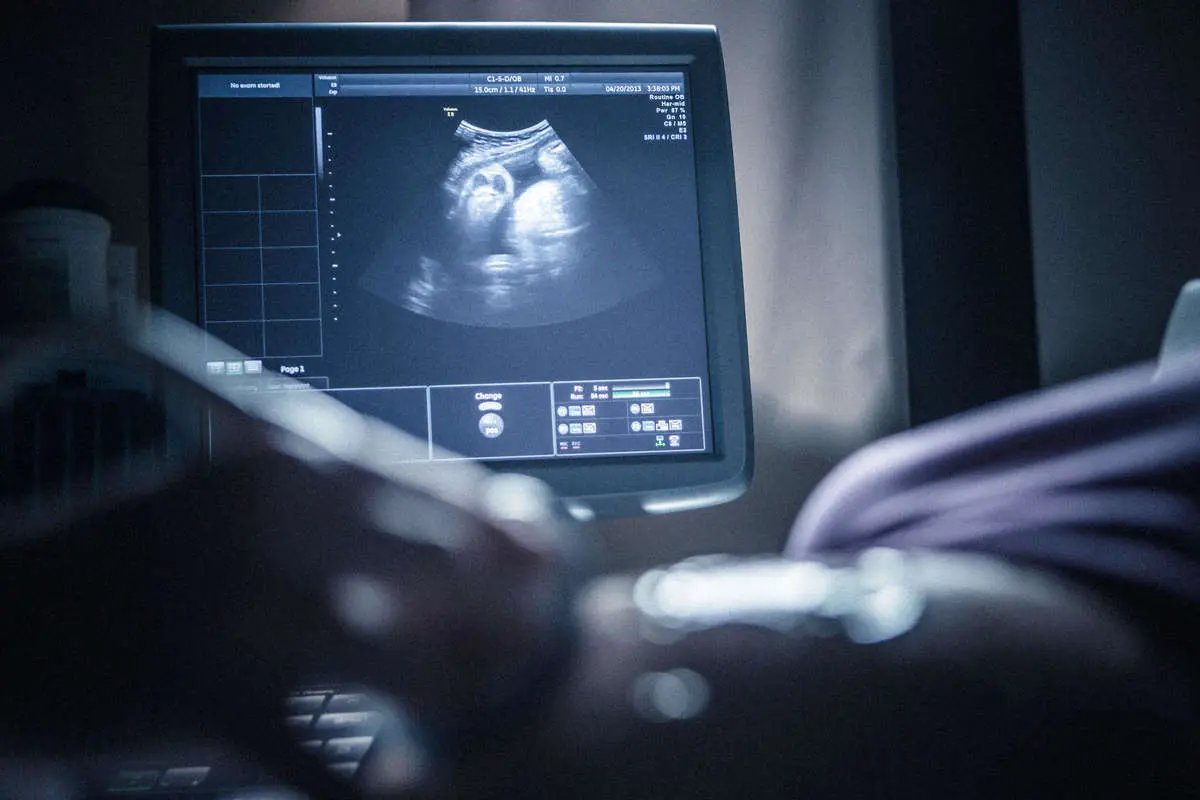

زهرا جعفری عضو هیئت تحریریه

طرح «جوانی جمعیت و حمایت از خانواده» باهدف افزایش نرخ باروری در سال ۱۴۰۰ تصویب و اجرا شد. این سیاست در واکنش به کاهش نرخ تولد و سالمندی جمعیت به اجرا درآمد و با محدودکردن غربالگری‌های پیش از تولد و ممنوعیت سقط‌جنین، همراه بود. بر اساس آمار و نتایج گزارش‌های منتشر شده توسط وزارت بهداشت و مرکز جوانی جمعیت، این سیاست نه‌تنها به هدف خود نزدیک نشد، بلکه پیامدهایی مانند افزایش تولد نوزادان مبتلا به سندروم داون، نقض حق بر بدن و سلامت زنان، افزایش هزینه‌های سلامت و...  را به همراه داشته است. سیاست «جوانی جمعیت و حمایت از خانواده» حالا به یکی از مناقشه‌برانگیزترین نمونه‌های سیاست‌گذاری جمعیتی در ایران تبدیل شده است و یادداشت حاضر سعی خواهد کرد این طرح را از منظر سیاست‌گذاری اجتماعی مورد تحلیل و ارزیابی قرار دهد.

ممنوع یا محدودیت اعمال غربالگری‌ در دوران بارداری از اصلی‌ترین تغییرات در سیاست حاضر بود. این تصمیم در حالی اتخاذ شد که پیش از آن، پزشکان موظف به تجویز غربالگری بودند و بخش زیادی از سقط‌های درمانی در چارچوب قانونی و پزشکی انجام می‌شد. اما با اجرای این ممنوعیت، احتمال تولد نوزادان با ناهنجاری‌های کروموزومی مانند سندروم داون دوبرابر شد و خانواده‌ها از استفاده ابزار پیشگیری محروم شده و در معرض بارداری‌های پرخطر قرار گرفتند.